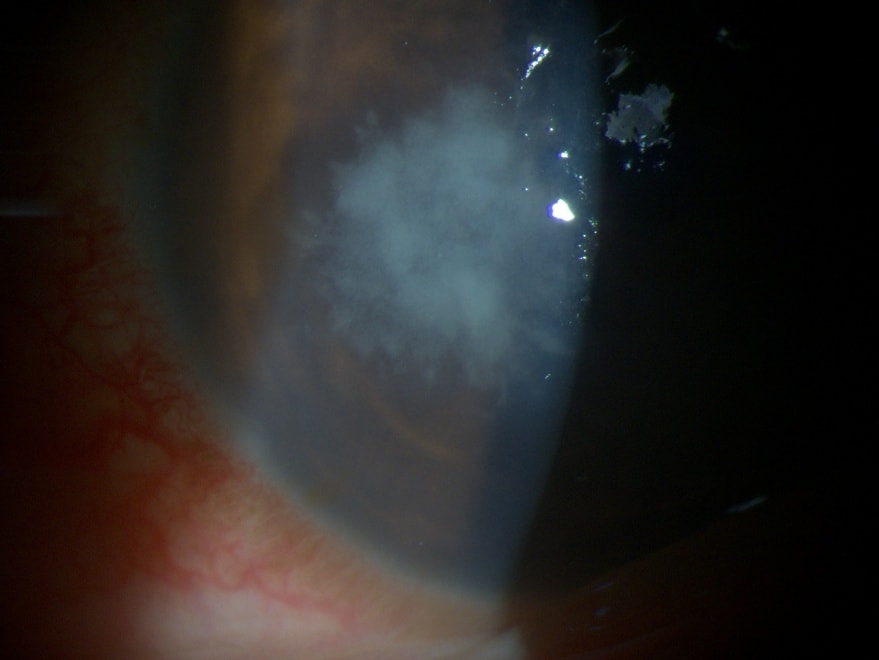

Bij opname was de toestand verergerd en werd bij de patiënt een vermoedelijke schimmelinfectie van het hoornvlies vastgesteld. Dit is een gevaarlijke complicatie die vaak een langdurige behandeling vereist en het risico op littekenvorming van het hoornvlies met zich meebrengt, wat het zicht ernstig kan aantasten als het niet goed wordt behandeld.